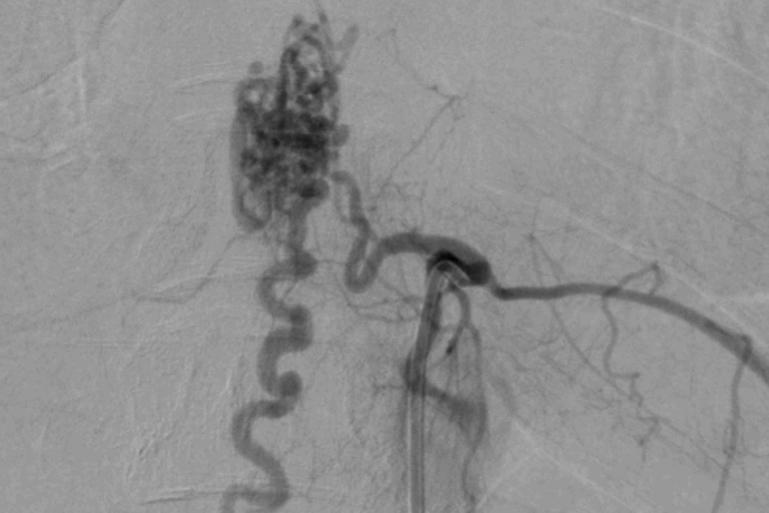

Ảnh chụp cho thấy khối dị dạng mạch máu tủy sống của nữ bệnh nhân (Ảnh: BVCC).

Bác sĩ Phạm Định Chương, khoa Nội Thần kinh của bệnh viện cho biết, bệnh nhân đã mắc căn bệnh dị dạng mạch máu tủy. Đây là một bệnh lý hiếm gặp, người bệnh có nguy cơ vỡ dị dạng gây xuất huyết tủy, phù tủy do tăng áp lực tĩnh mạch. Cả hai biến chứng này sẽ dẫn đến yếu liệt hai chi dưới, rối loạn tiêu tiểu, thậm chí nhiều trường hợp tàn phế phải nằm liệt giường. Chiến lược điều trị cho bệnh nhân là loại bỏ được khối dị dạng nhưng phải bảo tồn các động mạch nuôi tủy, đặt ra nhiều thử thách cho ekip can thiệp.

Người bệnh được điều trị bằng kỹ thuật đưa ống thông siêu nhỏ qua động mạch nuôi gập góc, ngoằn ngòeo để tiếp cận ổ dị dạng và bơm keo sinh học để tắc ổ dị dạng.

Sau khoảng 3 tiếng can thiệp, ekip loại bỏ được khối dị dạng, bảo tồn được các chức năng thần kinh, đặc biệt là chức năng vận động. Hậu can thiệp, chị S. có thể tự đứng và đi lại nhẹ nhàng, xóa tan nỗi lo bị liệt. Sau 5 ngày điều trị, người bệnh được xuất viện và tiếp tục tập vật lý trị liệu phục hồi chức năng tại nhà.